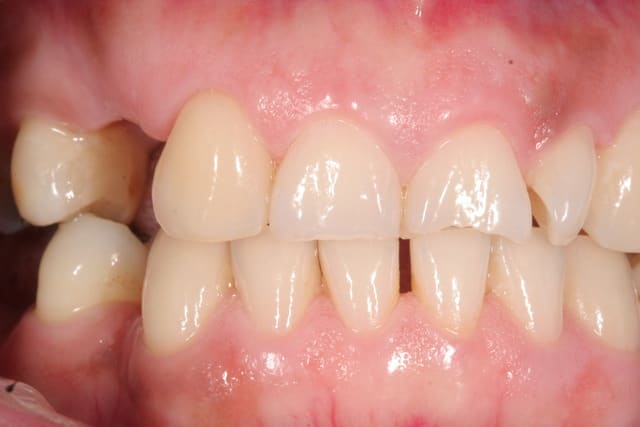

J'avais du les passer déjà quelque part ici. Travail fait en une journée sur 10 dents. J'ai perdu la photo avec écarteur du travail fini, mais cela tombe bien car j'avais pas un très bon maquillage des collets. Ceci dit, patiente AVC avec sourire comme tu vois.

A3 zaw6gr - Eugenol

A7 kn2z0z - Eugenol